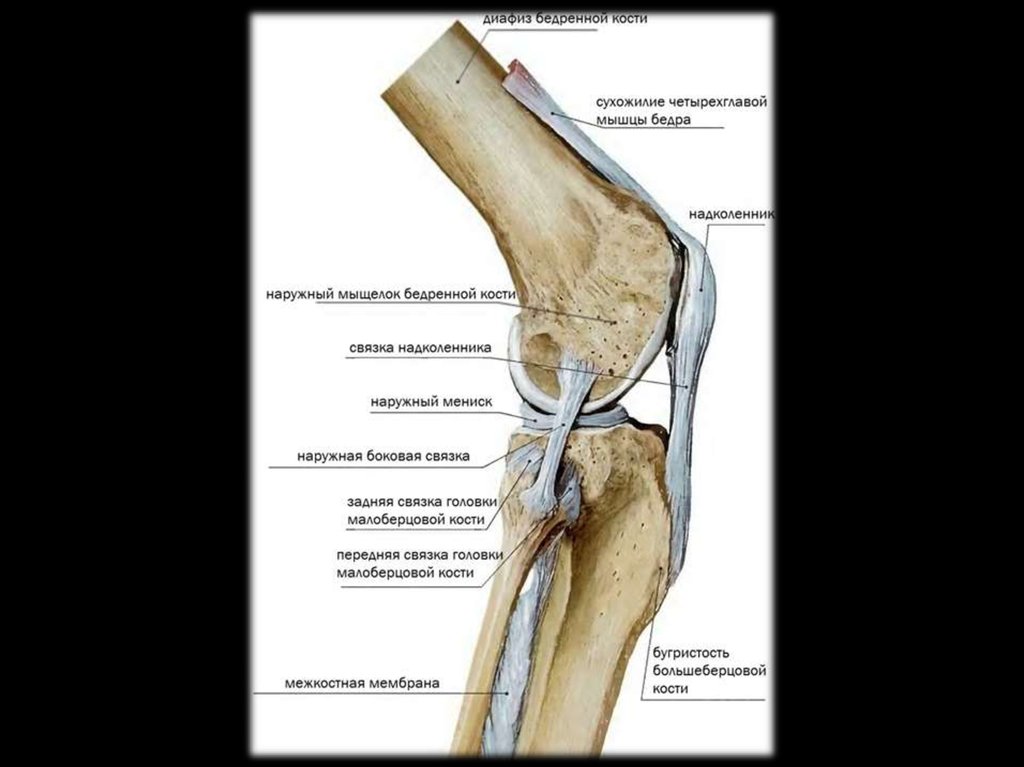

41. Лигаментит большеберцовой связки коленного сустава

42.

Здоровый сустав

Выраженные

изменения